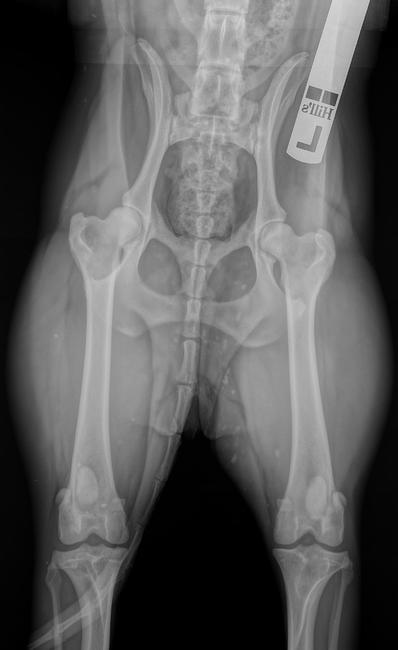

Tynam:

hij ligt wat scheef. Maar als je kijkt naar de gaten van de heupen zijn deze even groot (en dat is niet zo als hij scheef zou liggen). En het middelpunt van de heupkoppen ligt bijderzijds zo te zien mooi binnen de kommen.

Uhh is die van Tynam opgestuurd??

Deze ligt enorm scheef en de knieën zijn niet echt ingedraaid...